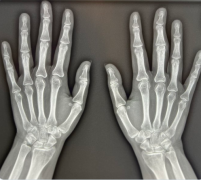

X射线有哪些应用?

X 射线具有穿透性、荧光效应和感光效应等特性,使其在医学、工业、科研等多个领域都有重要应用,以下是一些主要的应用方面: 医学领域 诊断疾病 X 线摄影:可对人体骨骼、胸部等...更多 -